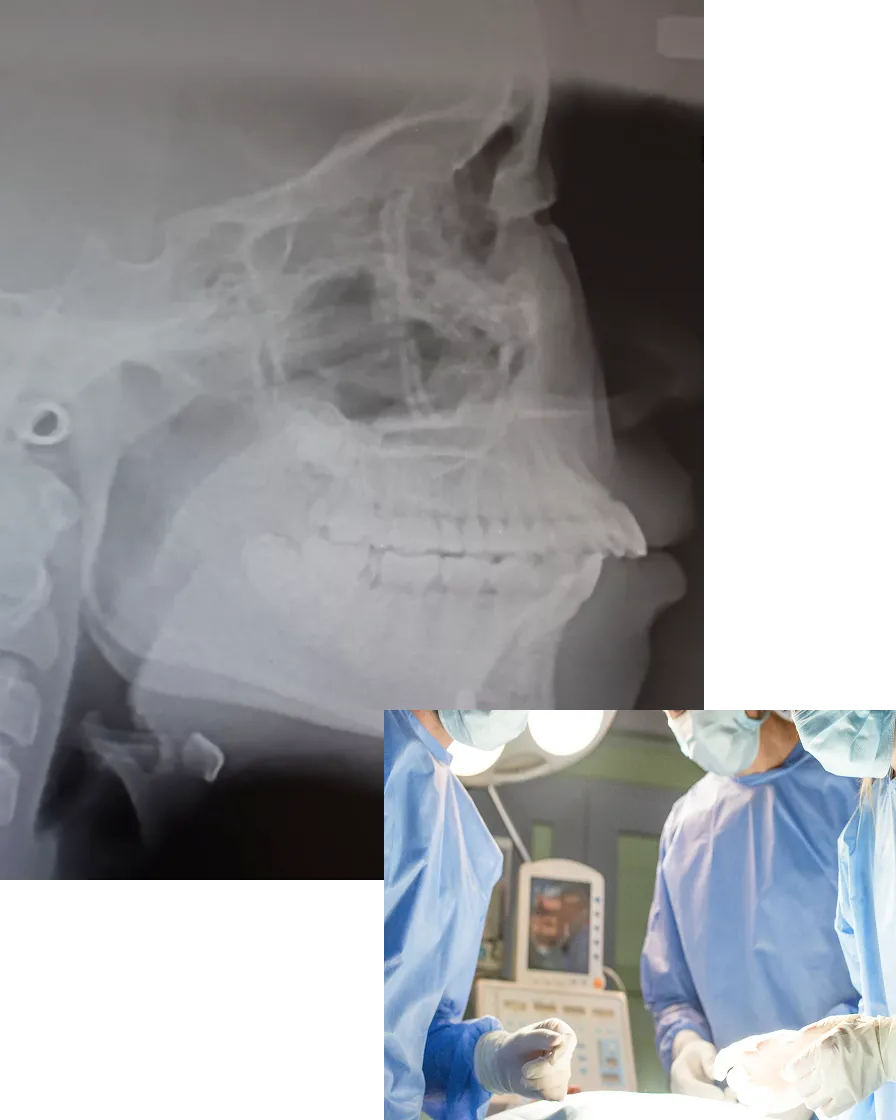

「全身麻酔がこわい」「術後はどうなるの?」そんなご不安にも、はじめの相談から丁寧にお応えします。CTやレントゲンを活用して変化を見える化しながら、治療の流れ・手術内容・過ごし方までわかりやすくご説明いたします。

レントゲン、CT撮影、口腔内スキャン、写真撮影、歯型採取などを行い、骨格・歯並び・噛み合わせ・顔貌バランスを多角的に分析します。